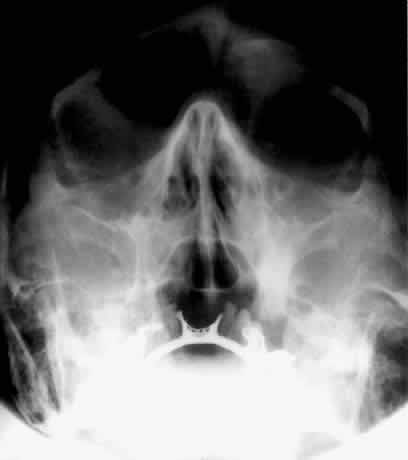

The orbital floor consists of the maxillary, zygomatic, and palatine bones. The floor is thinnest medial to the infraorbital canal, which is the location of most orbital floor fractures (Fig. 7). As mentioned earlier, the floor slopes upward from the lateral to the medial wall. The floor extends toward the orbital apex but does not reach the apex. This orientation of the floor makes frontal projections more informative than the lateral projection.

Fig. 7. A patient involved in a motor vehicle accident who sustained a right orbital floor fracture. Soft tissue density (arrow) located in the roof of the maxillary sinus. Disruption of the orbital floor is seen at the fracture site.

Waters view gives the best image of the anterior and middle portion of the floor. This is possible because extension of the neck brings the floor into a position that is tangential to the x-ray beam. The floor is represented by the most inferior radiopaque line, whereas the orbital rim will be the line above it.10 The vertical distance between these lines should be approximately 1 cm.19 This relationship between the floor and the orbital rim should be symmetric between the two orbits. Any asymmetry should suggest a fracture of the orbital rim or floor.